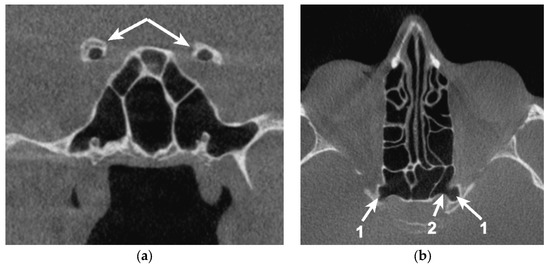

Cases of extended pneumatization within the LSW may determine the extension of inflammation and spread of infection in the ICA and the cavernous sinus [2,18] or a decrease in visual acuity by developing orbital cellulitis [9,10]. Bilateral OS pneumatization and a high degree of communication between paranasal sinuses could entertain the possibility of neurovascular structures from both sides being affected simultaneously (Figure 6).

Figure 6. Sagittal CBCT reconstruction, demonstrating the topography of the left optic canal (OC) neighboring the extension of the right sphenoid sinus (false Onodi). 1. Extension of the right sphenoid sinus; 2. Left OC.